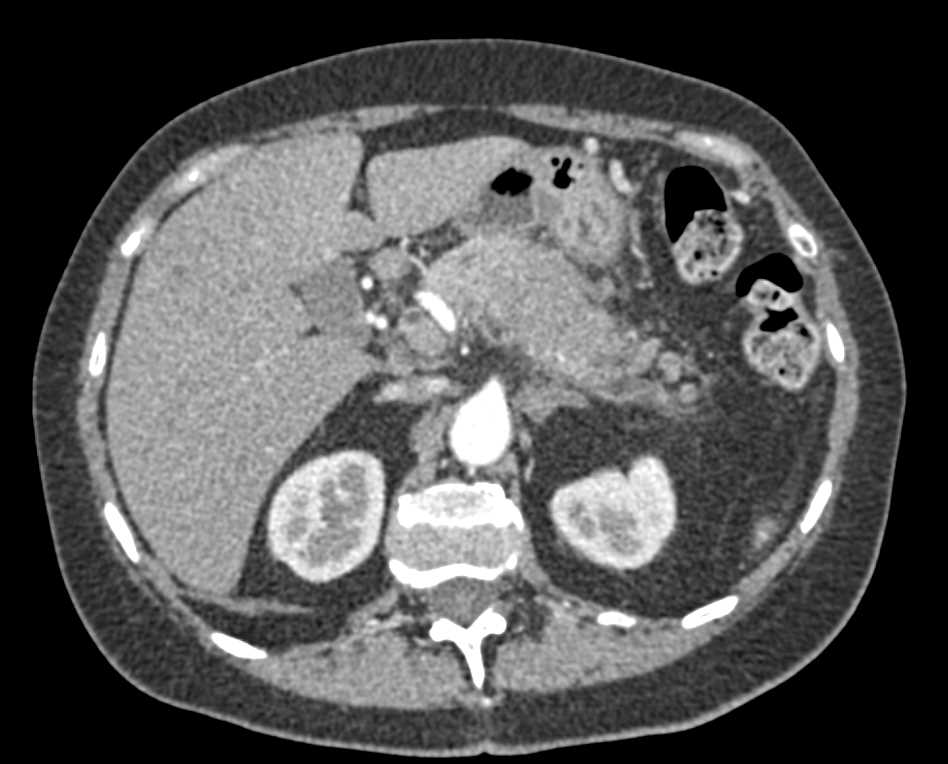

Pancreas Adenocarcinoma